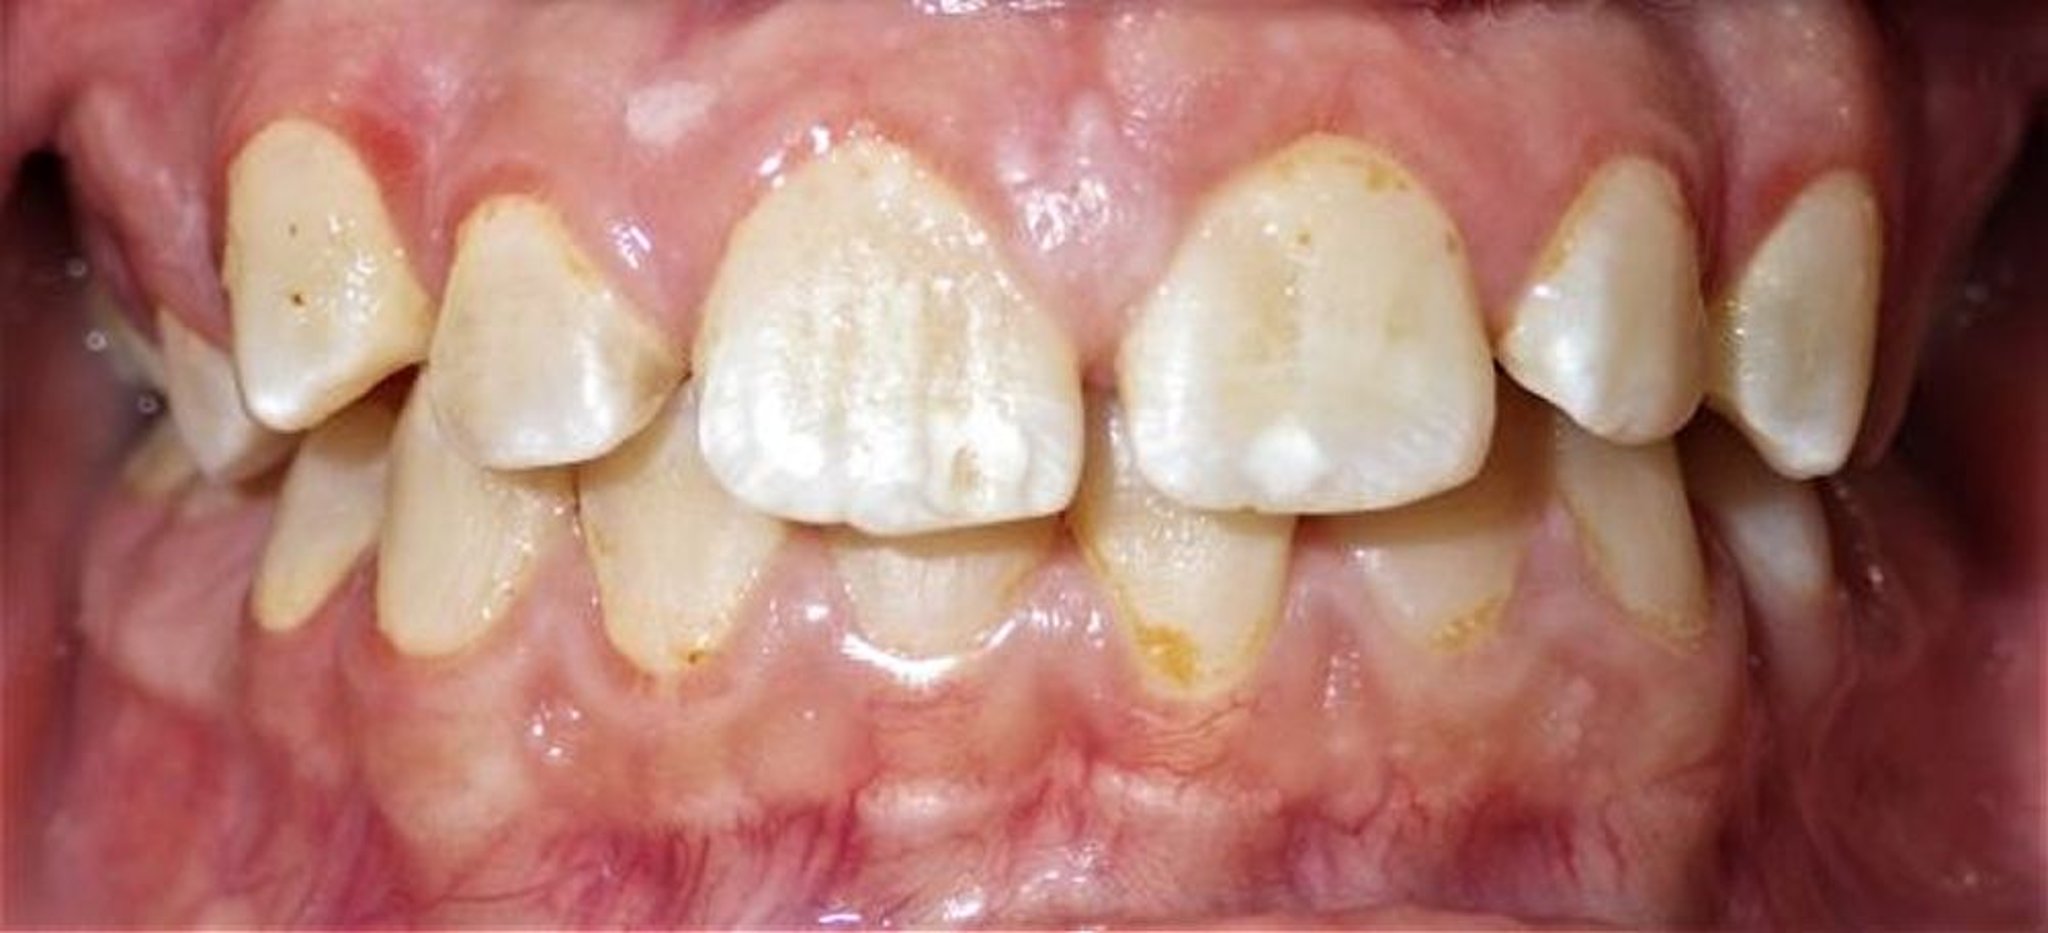

Gingivitis

Esta imagen de gingivitis en un joven muestra inflamación de las encías marginales (las más cercanas a los dientes), con edema de las papilas interdentales e inflamación a lo largo de los caninos superiores.

Image courtesy of James T. Ubertalli, DMD.